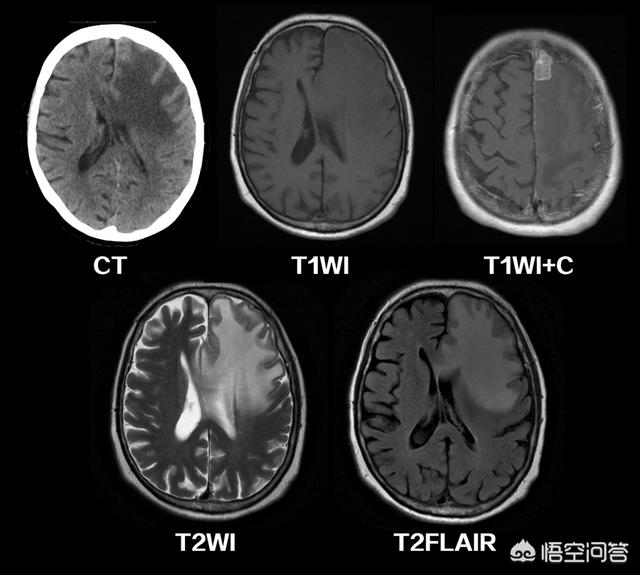

(血管源性脑水肿,CT和不同形式磁共振扫描的结果对比。)

CT和磁共振各有优缺点:

优点:价格相对要便宜一些,检查速度快,用于急诊检查更方便。比如患者如果有脑出血、颅内骨折、只需要几分钟就能看到结果,便于我们迅速进行下一步诊治。

缺点:对于软组织的解析能力相对要差一些。

缺点:价格相对高一些,检查麻烦,速度慢。大多数情况下,检查需要预约,难以应用于急诊抢救(看骨质,看脑出血都不如CT清楚)。如果患者体内有金属植入物,有可能做磁共振也会受到限制。

优点:对软组织的解析力好于CT,比如早期的脑梗塞CT上可能看不出来,但是磁共振却很清楚。,看脑肿瘤、脑炎、脑白质病等脑内病变,也优于CT。有时候还能分析组织的代谢活动情况。